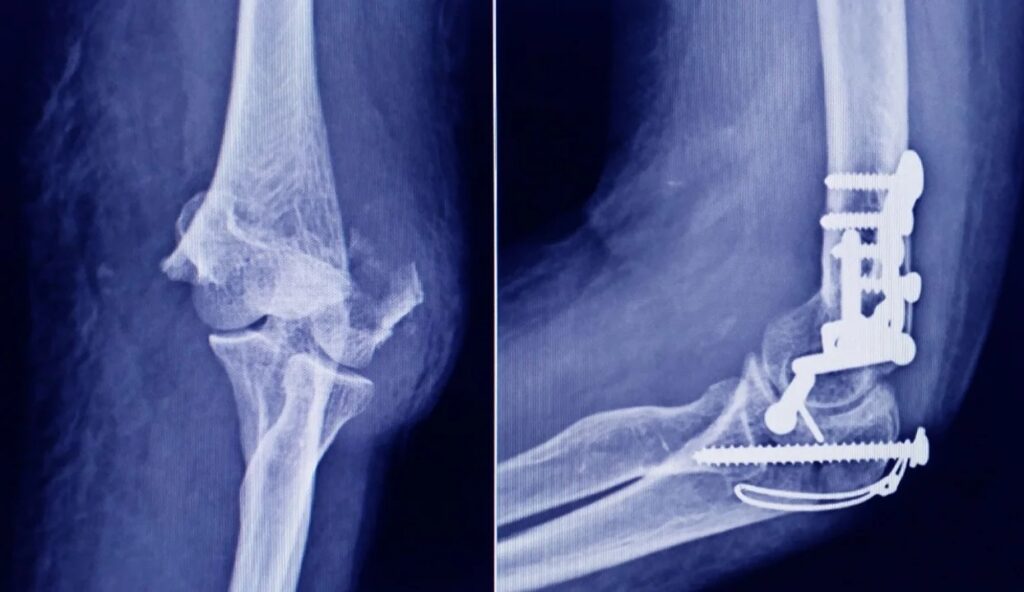

Según detalló la Anmat, el dispositivo corresponde a un tornillo tipo «twist-off» (o snap-off), utilizado en cirugía traumatológica para fijar pequeños fragmentos óseos y realizar osteotomías o fusiones en pies, tobillos, manos y muñecas.